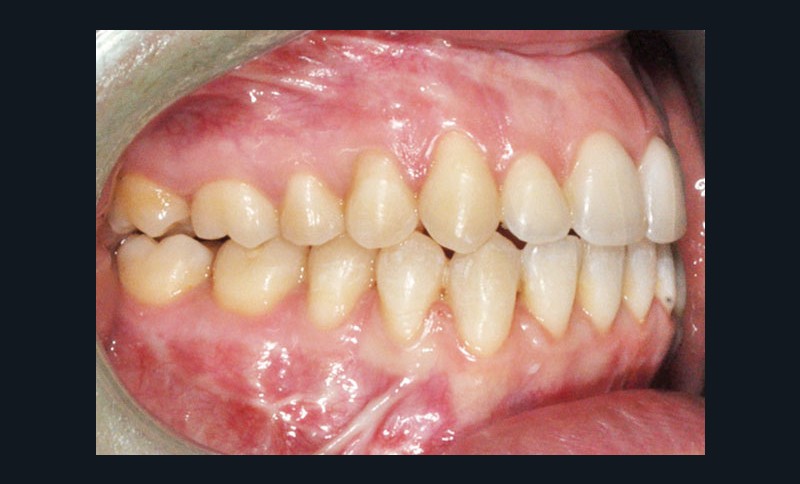

Diagnostic (fig. 1)

Cette patiente de 29 ans consulte pour des raisons principalement fonctionnelles mais également esthétiques. Elle présente :

– une classe II squelettique hyperdivergente

– une endognathie maxillaire

– une classe II division 1 majeure et asymétrique associée à une béance antérieure sévère

– un profil très convexe avec une occlusion labiale difficile et une biprochéilie

– une DDM par défaut modérée, maxillaire et mandibulaire

– des troubles de la posture et de la fonction linguale.